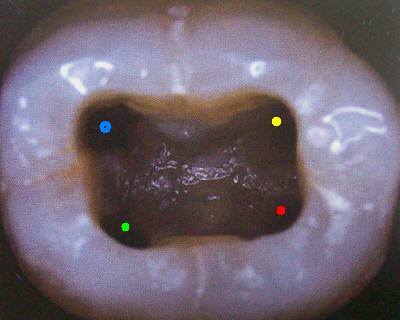

Primer Molar Inferior

Esta pieza dentaria es la más voluminosa de la arcada. Posee por general dos raíces bien definidas una mesial y otra distal, ambas aplanadas en sentido mesiodistal. La raíz mesial presenta una curvatura acentuada, mientras que la distal puede ser algo curva o recta.

Cuando tiene tres conductos el mas amplio es el distal con una sección oval y su curvatura es suave o recta. Si presenta cuatro conductos la raíz distal contendrá dos de ellos y son de diámetro más pequeño y en caso de presentar dos conductos, ambos son amplios.